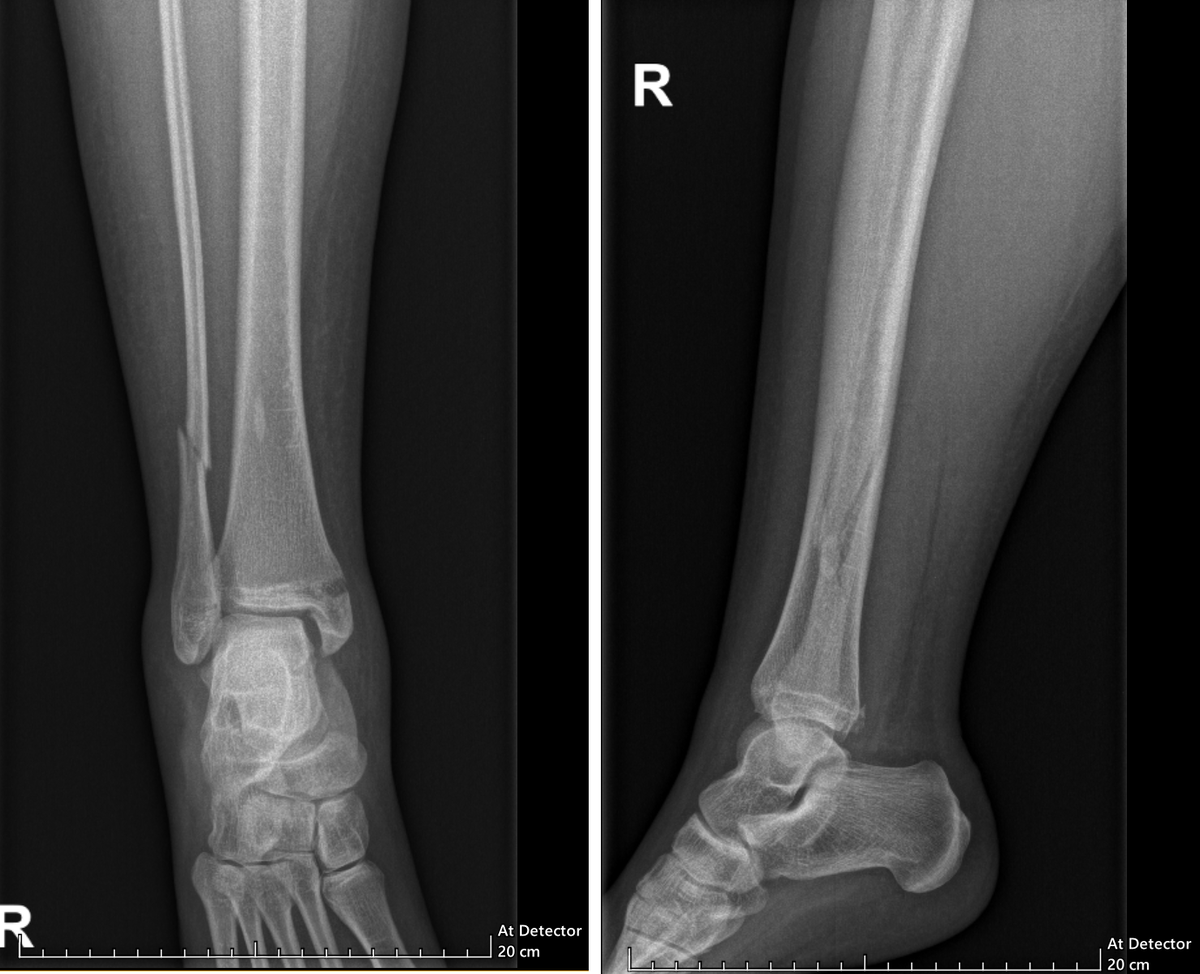

11 августа 2025 года я сломала ногу при самостоятельной посадке на параплане в Чегеме, 18 августа мне успешно собрали ногу обратно в Склифе. Прошло уже 2 месяца с операции, скоро уже будет вторая плановая операция. Пришло время поделиться тем, как у меня идут дела на реабилитации. И идут они хорошо. Если не читали предысторию, ссылки оставила в конце. Там всё: как сломала ногу, как местные СМИ всё переиначили на свой лад (и как всё было на самом деле), как мы выбивали у АльфаСтрахования трансфер из Нальчика в Москву – короче, рекомендую потом почитать. Для меня опыт подобной иммобилизации и такого серьезного перелома был первый (и надеюсь, что последний). До этого все приключения обычно заканчивались очередным шрамом, ушибом, синяком, ссадиной. Руку ломала всего 2 раза, так что тут мне хвастаться нечем. А тут я познакомилась со новыми прелестями жизни: отекшая нога, сложности в самообслуживании, бессонные ночи из-за болей, бытовая недееспособность — короче, ставлю этому опыту ноль из д

11 августа 2025 года я сломала ногу при самостоятельной посадке на параплане в Чегеме, 18 августа мне успешно собрали ногу обратно в Склифе. Прошло уже 2 месяца с операции, скоро уже будет вторая плановая операция.

Риск повреждения позиционного винта присутствует всегда. Сломанный винт вытащить целиком можно, но это всегда вопрос рисков и жизненной необходимости. И если уж такое случится, подарочный кусочек металла в кости не создаёт много проблем: фотографируй его на рентгене иногда и всё.

В моём случае этот риск немного повышен из-за телосложения и отягощенного анамнеза, но он некритический. Если не скакать аки горная коза на больной ноге, не падать на неё, ставить ровно, не делать скручивания и аккуратно ходить по неровным поверхностям, то причин резко сломаться для винта нет.